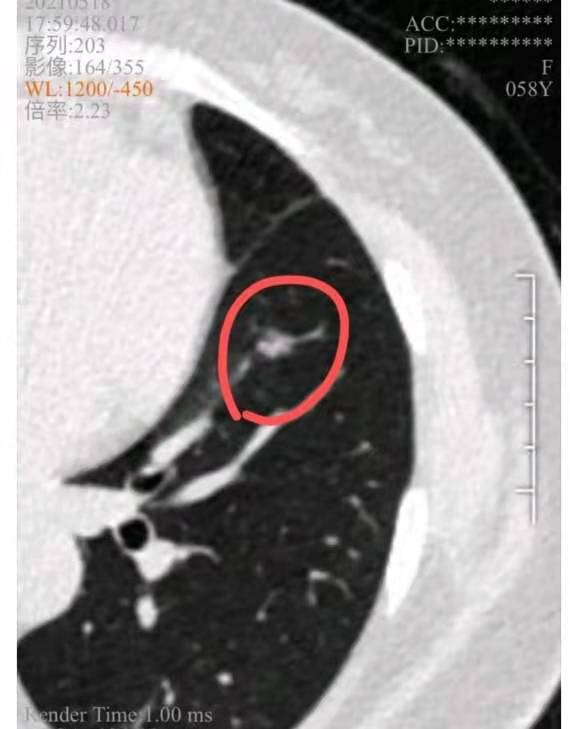

做好多发磨玻璃结节手术的前提是精准诊断,首先要准确分清楚哪些结节是有问题的,哪些结节是肯定良性的。比如医生告诉您,这个小的结节肯定良性的,就是非典型增生,可以肯定10-20年都不会有问题,而且还位置深需要切很多肺,那确实可以不切。其次就是认真阅片别漏诊,看到过太多抓小放大找我求诊的病例了。比如下面举例这例:切掉的是原位癌,留下的是至少微浸润腺癌。

戴主任您好!我2020年6月在上海某医院做手术切除左肺上叶两个结节,术后大病理是原位癌。2020年12月31日复查发现左肺下叶7mm磨玻璃结节(手术前就有,医院漏掉的),2021年5月复查, 结节已经长大至9mm,有分叶和血管穿行 ,右肺中下叶各有一个4mm的磨结,医生说手术可以再等等。恳请戴主任帮帮我,给这个高危磨玻璃结节定个性。我还能观察多久?如果手术我想去重庆找您手术。谢谢!

至少微浸润腺癌,可以手术,也可以再随访一段时间再手术。术前真有吗!这么大的结节,漏诊了?